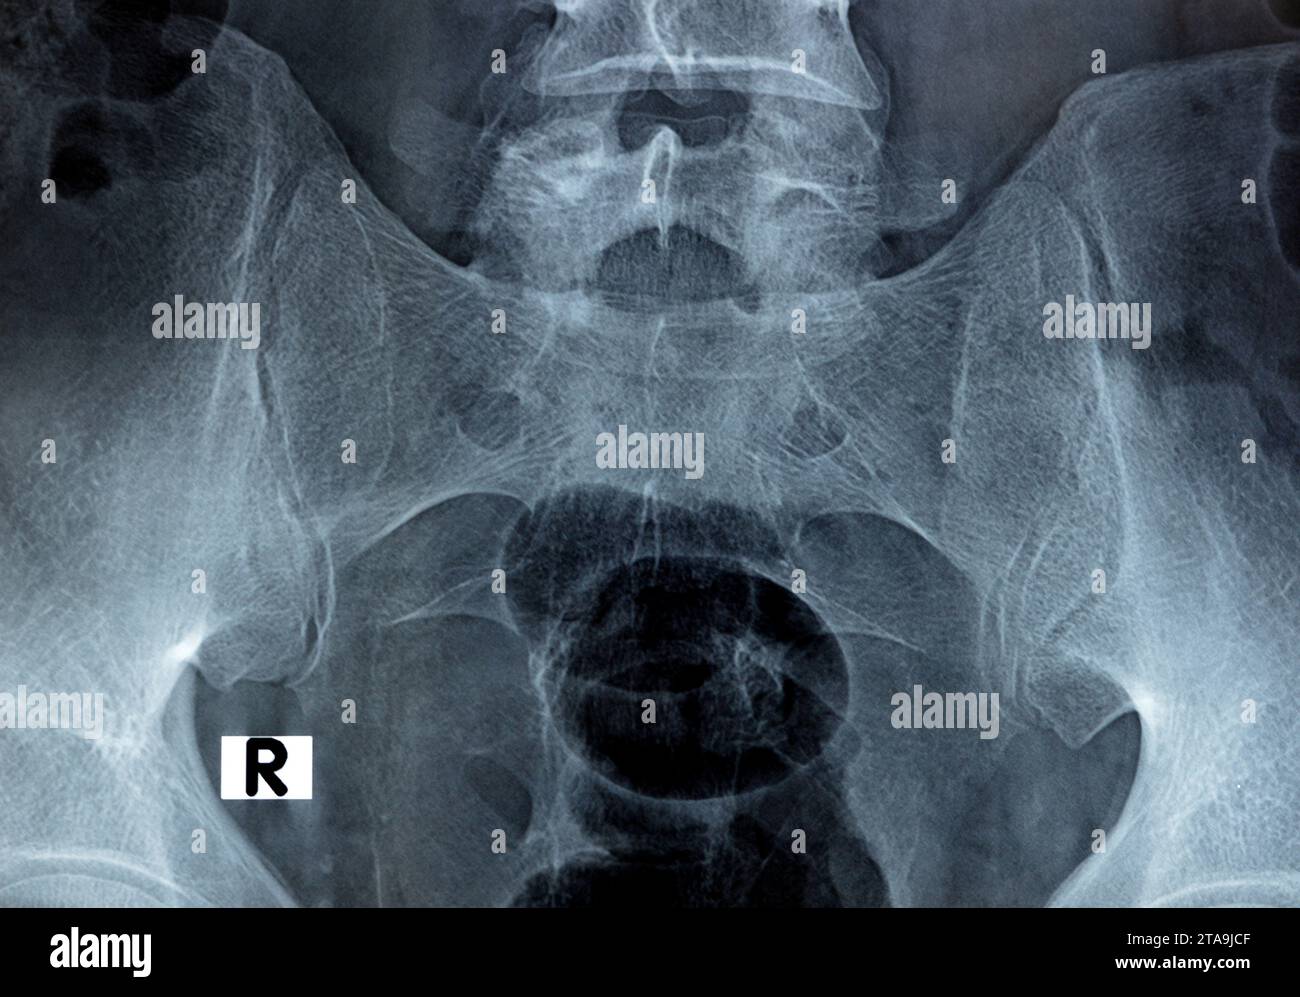

Si Joint Xray Images . Si joint blocks may be used to identify si joint pain. The sacroiliac joint anteroposterior (ap) oblique view of the sacroiliac joint is one of the projections that make up the sacroiliac series. This projection examines both left and right. Sacroiliitides) is an inflammation of one or both sacroiliac (si) joints. It is a common cause of. In mri, active inflammation of sacroiliac joints is indicated by the presence of subchondral bone marrow edema, synovitis,. The central role of imaging in diagnosing disorders affecting the sacroiliac joints (sijs) necessitates a comprehensive understanding of the advantages, limitations, and potential pitfalls of the imaging techniques that can be used. Correct central ray angulation when sacroiliac joints spaces and the l5 to s1 junction and sacral foramina should appear open.